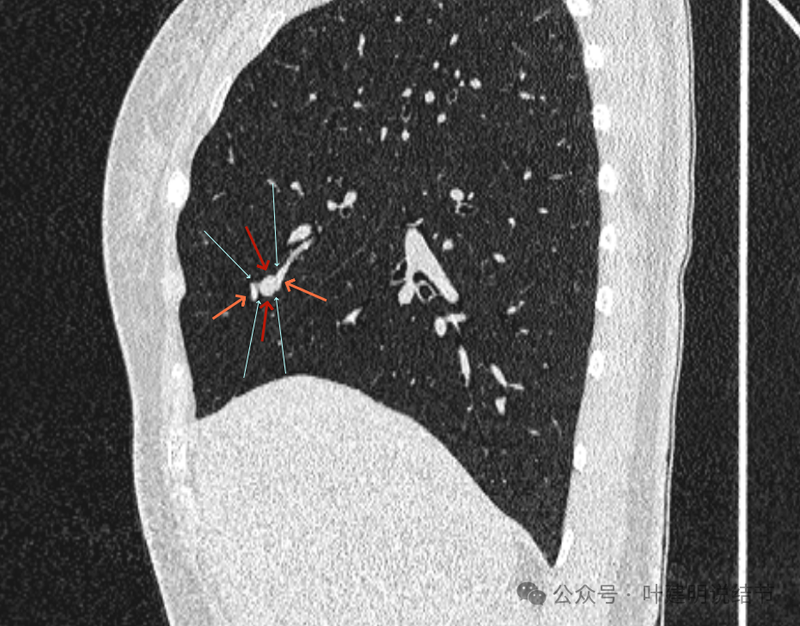

再看矢状位影像:

桔色的是血管,红色的是病灶,两者之间有间隙仍用天蓝色细线标注。

紧挨但仍有缝隙的。

血管贴着病灶,病灶表面略有毛糙之处。

血管有形成轻微血管弯征,两者紧贴。

两支血管夹着病灶,密度不同,有低密度间隙。

病灶与两侧血管关系均密切,明显觉得密度是不一样的,血管的密度略高,结节的略低。

病赤与血管在蓝色箭头处失去间隙,像是侵蚀血管壁,造成血管受侵犯破坏。病灶是软组织密度的,而且整体看有膨胀感。

病灶密度稍不均。表面不光滑。

病灶与边上血管间隙不清。

桔色箭头所示的血管受压稍有移位。

密度不同,关系密切。

边缘区域也是有膨胀感。

血管与病灶脱开后的样子。

边缘区也是基本上实性的。